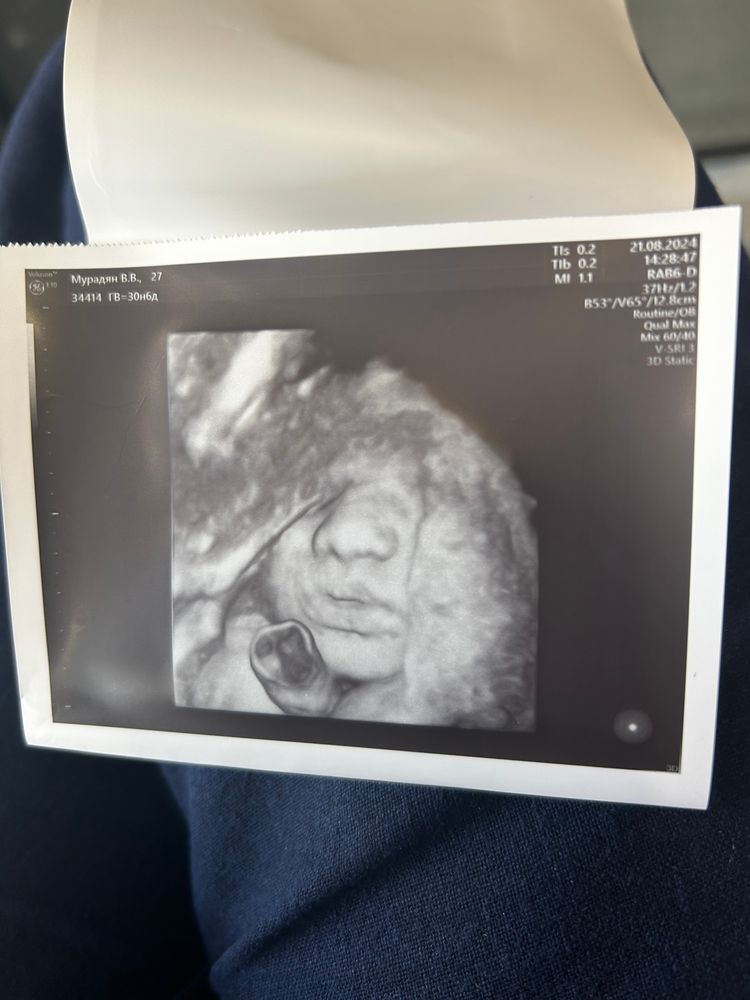

31 неделька , 3 ий скрининг 💖

Вес сыночка 1 кг 720 грамм, по скринингу все хорошо) не хотел лицо полностью показывать, лежит малыш в головном уже, до встречи осталось совсем немножко ❤️